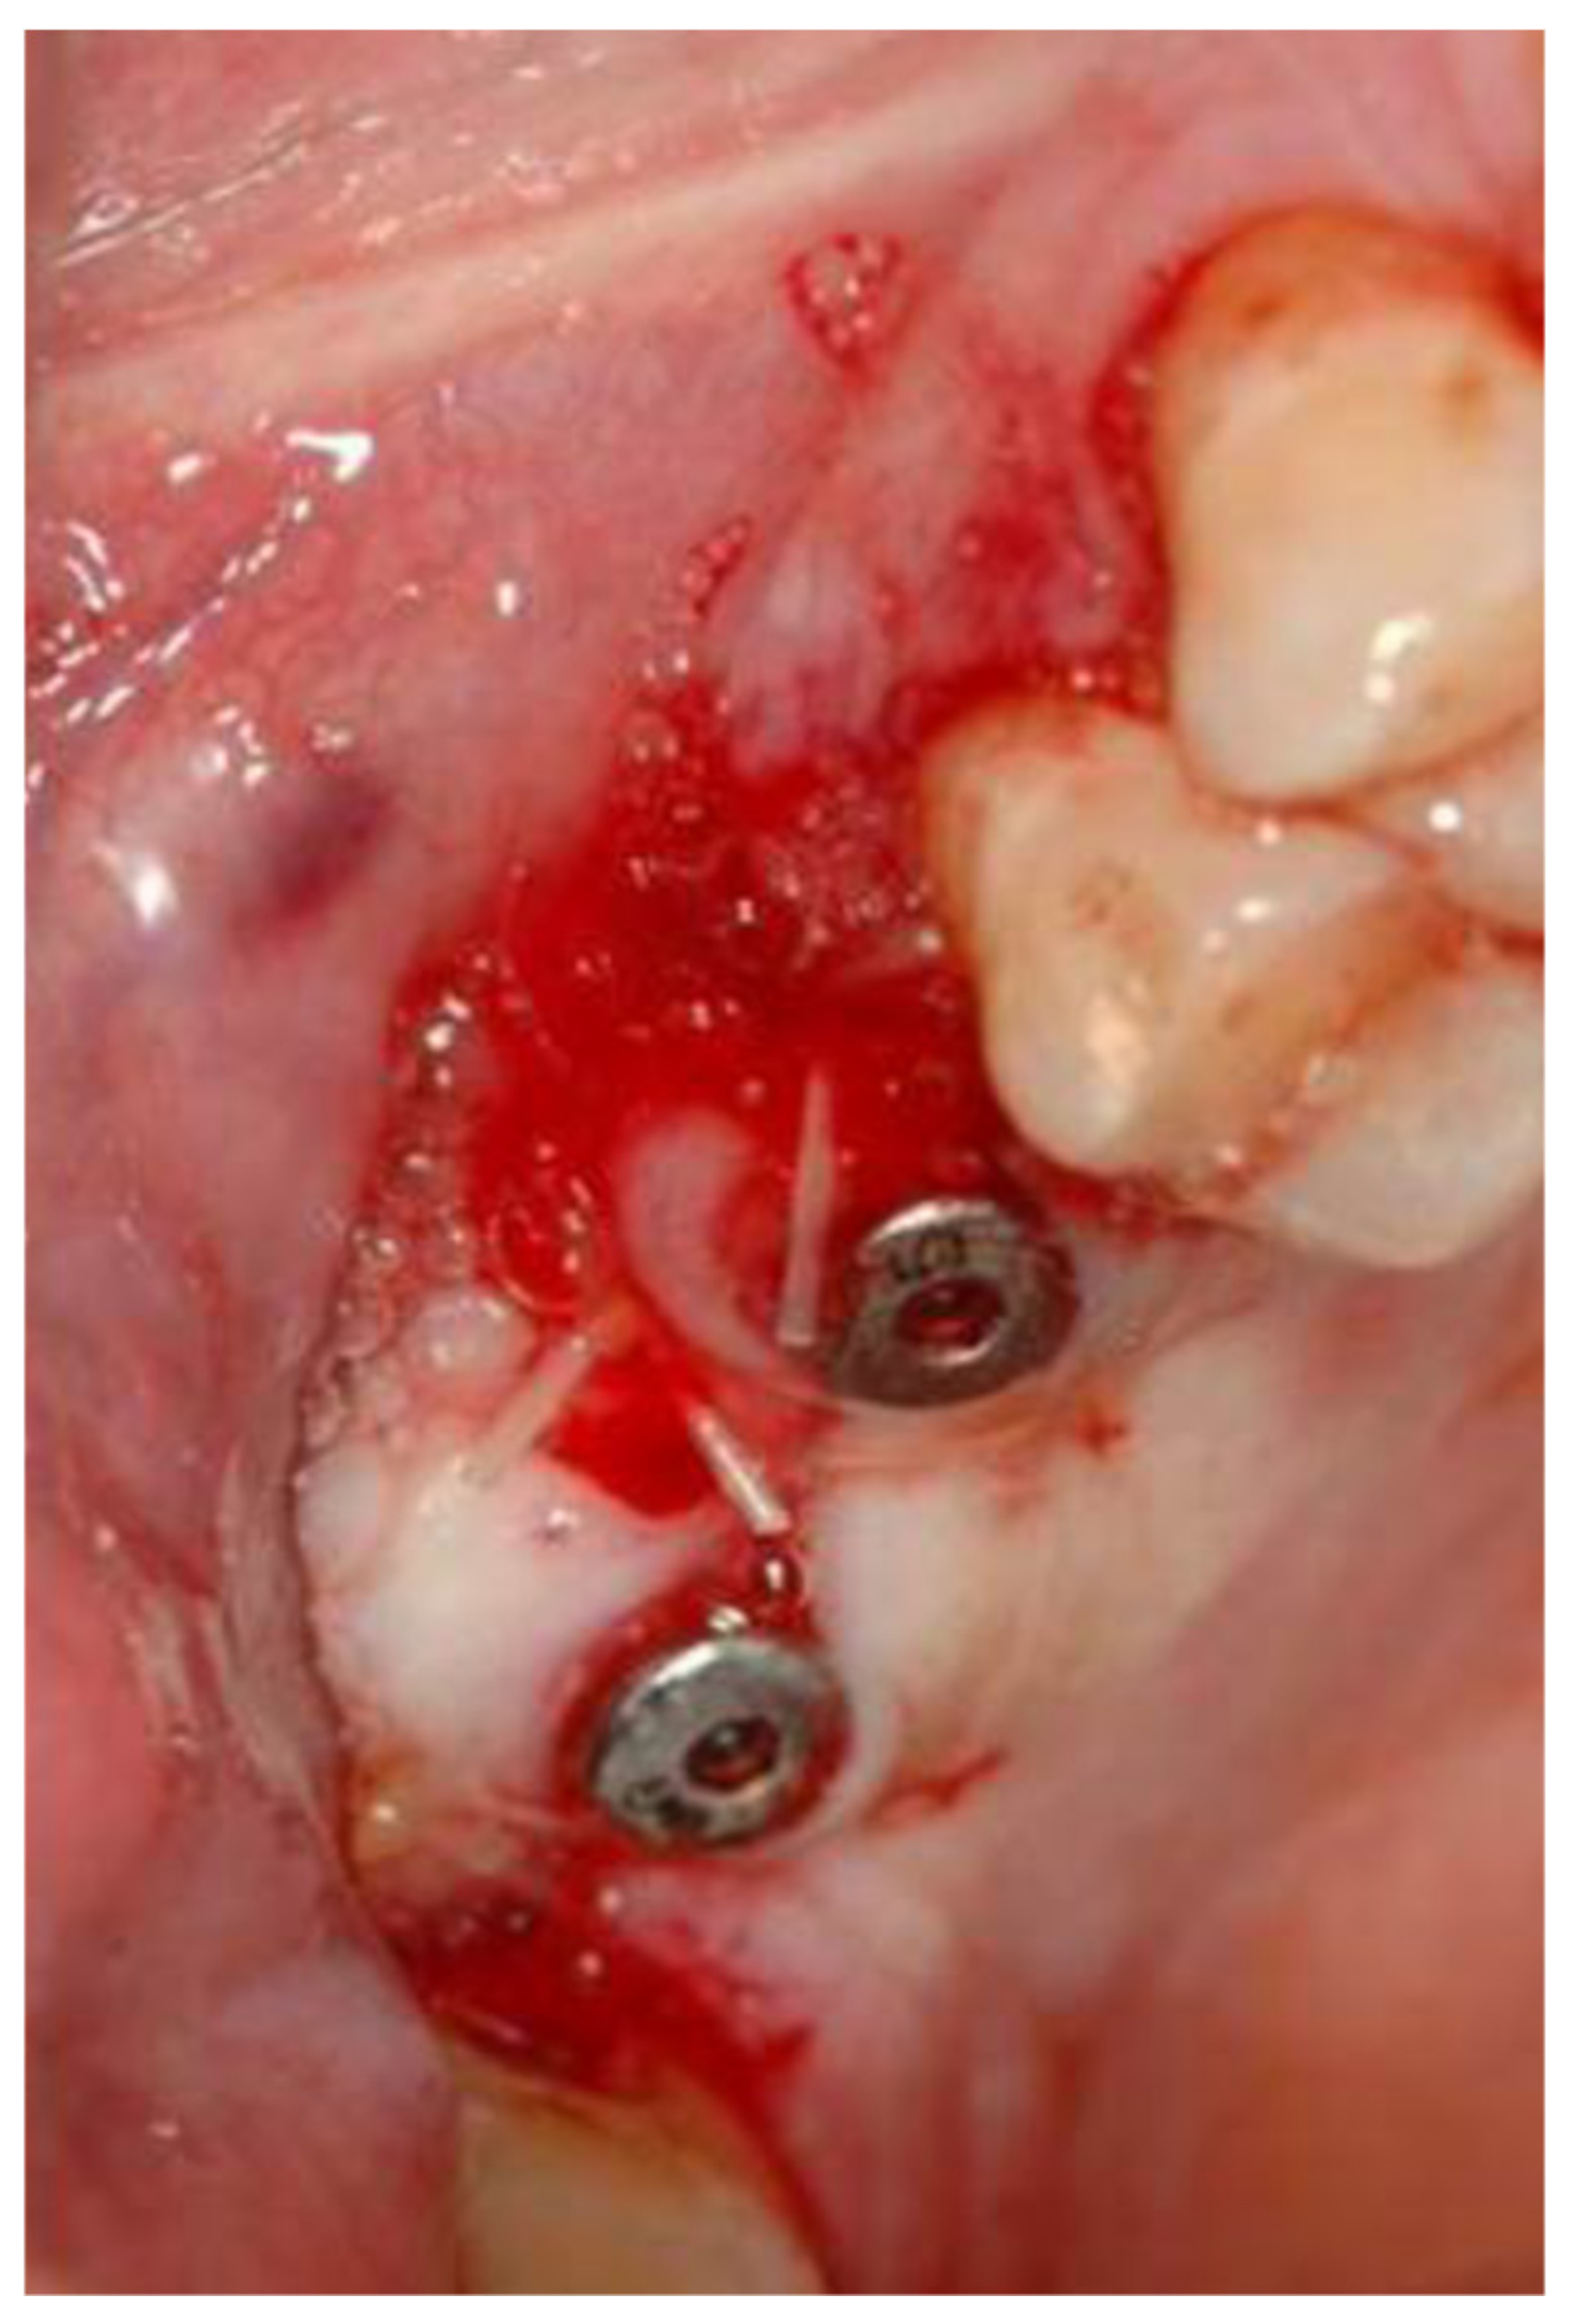

2.1. Standard Surgical Procedure